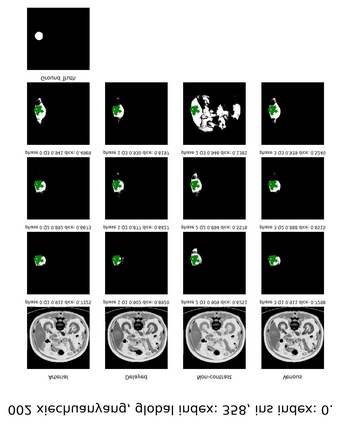

Learning to segmentation without large-scale samples is an inherent capability of human. Recently, Segment Anything Model (SAM) performs the significant zero-shot image segmentation, attracting considerable attention from the computer vision community. Here, we investigate the capability of SAM for medical image analysis, especially for multi-phase liver tumor segmentation (MPLiTS), in terms of prompts, data resolution, phases. Experimental results demonstrate that there might be a large gap between SAM and expected performance. Fortunately, the qualitative results show that SAM is a powerful annotation tool for the community of interactive medical image segmentation.